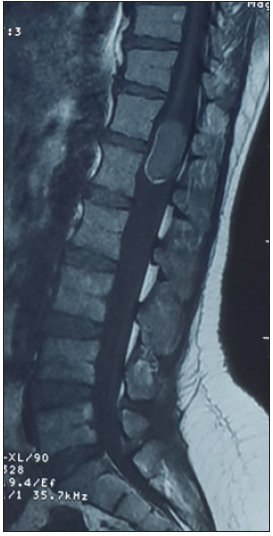

A 37-year-old woman presenting with low backache, and progressive weakness of both lower limbs for 5 months. On clinical examination, she had features of a conus medullaris syndrome with grade 4 power in both lower limbs, positive Babinski sign bilaterally, while abdominal reflexes and anal tone were normal without tuft of hair or a patent dermal sinus tract. A magnetic resonance imaging MRI showed cord expansion at the tip of the conus medullaris with a heterogeneous lesion hyperintense on T1 and hypointense on T2 images. In addition, contrast enhanced images with gadolinium revealed an intramedullary lesion at T12 L1 segment (Figure 1). After laminectomy, a midline myelotomy was performed and revealed a whitish and yellowish mass with a well-defined adherent capsule to spinal tissue followed by micro-dissection of the cyst wall allowing complete removal of caseous cystic contents with adequate conus decompression (Figure 2). Pathological examination confirmed the diagnosis of dermoid tumor, showing stratified squamous epithelial cells with underlying fibrous connective tissue containing hair follicles, keratin and sebaceous glands. The patient recovered well from the procedure, her back pain had not recurred, and she remained independent postoperatively.

Figure 1a:

Figure 1c: Spinal MRI sagittal T1 (a), T1 postcontrast (b) and axial T2 (c) showing an heterogenous lesion hyperintense T1, hypointense T2 of the conus at T12 L1 level.